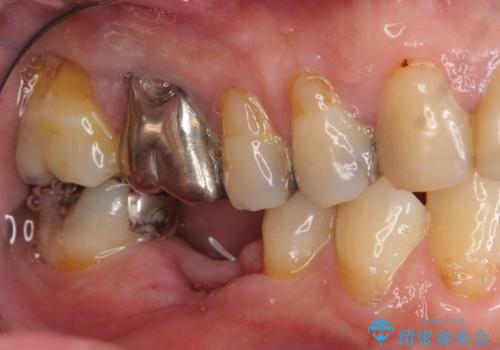

- 銀歯がダツリし、支える歯が破れている状態で抜歯を余儀なくされました。

短期間での咬合昨日の回復、手術を希望されなかったのでブリッジによる咬合機能回復を計画します。

かみ合わせが強いのでフルジルコニアクラウンベレッツァを用いたブリッジを製作。